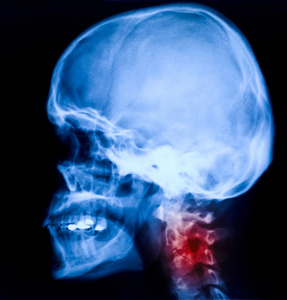

X 線頸部和頸椎側面的看法頸部疼痛神經根壓迫手手腕或手指麻木的患者的放射影像圖像照片檔及更多人照片